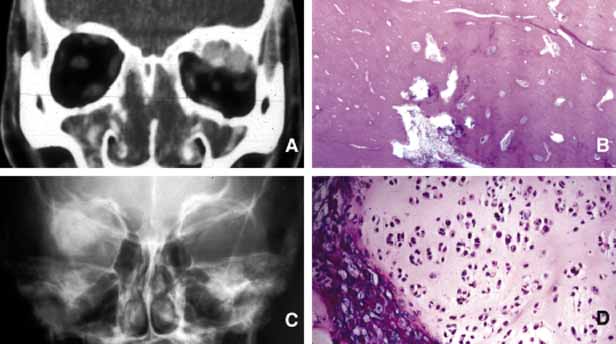

Mucocele

Although a commonly encountered space occupying lesion in the orbit, mucocele is technically not a neoplasm. It is a cystic cavity lined by pseudostratified respiratory epithelium prolapsing into the orbit from a paranasal sinus, most commonly the frontal followed by the ethmoidal sinus (Fig. 5). Primary mucoceles develop as a result of an inflammatory obstruction of the ostium of the paranasal sinuses. Secondary mucoceles, however, are most commonly seen after orbital trauma and surgery; they may also develop secondary to neoplasms of paranasal sinuses and nasopharynx. If there is a superimposed infection, the lesion is referred to as pyocele. The mucocele develops as a well delineated cystic structure originating from a paranasal sinus. Depending on the location, it may compress orbital structures including extraocular muscles, optic nerve, and the globe.41 Clinical presentation of the mucocele is usually with globe displacement and/or proptosis, extraocular motility deficiency, particularly in the direction of the sinus extension into the orbit, and other compressive symptoms.42 The crepitant or calcified hard wall of the mucocele may be palpated underneath the superior or medial orbital rim. Mucoceles in general, are rare in children, however, a unique variant, ethmoidal mucopyocele, is known to occur in the medial canthal area, with lateral displacement of the globe.

Fig. 5 Mucocele. Moderate proptosis and slight lateral displacement of the left eye secondary to a large medially located mucocele (m) originating from the ethmoid sinus (A,B). Note the compression of the calcified wall of the lesion onto the globe and the optic nerve (B). The large cystic nature of the mucocele with low internal reflectivity and segmentally calcified wall is demonstrated by ultrasonography (C). Gross specimen of the stripped mucosal lining of the mucocele from the same case (D).

On CT, mucoceles present as hypointense, expanding masses originating from the paranasal sinuses. Early in their development these lesions are small, mucous-containing cysts. Later they are characterized by crescent-shaped and thinned remodeling of the bony walls of the orbit and sinuses.43 On MRI, mucocele presents with different appearances depending on the amount of free water within its luminal contents. When the intraluminal mucous becomes inspissated, the signal intensity in both T1 and T2 images decrease, getting closer to normal air content of the sinus.44 Treatment of mucocele is surgical excision.